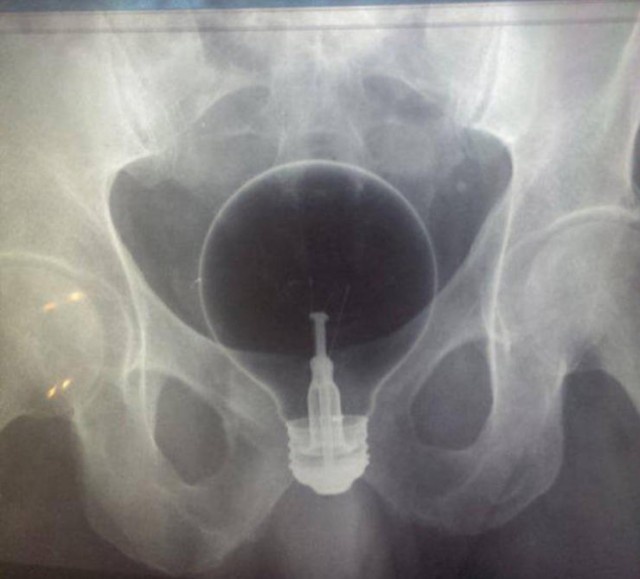

・電球、特大サイズの